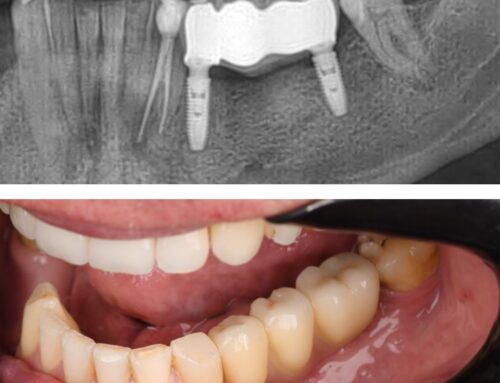

Razlika počinje brigom za točnu sliku stanja. RTG dijagnostika visoke rezolucije, CBCT snimke i intraoralni skeneri omogućuju stomatologu da vidi ono što klasičan pregled propušta. Digitalni otisci zamjenjuju neugodne kalupe, skraćuju vrijeme i povećavaju preciznost. Na temelju tih podataka izrađuje se individualni plan terapije: od endodoncije do implantologije i dentalne protetike. Kada je plan jasan, pacijent razumije svaki korak postupka i lakše se odlučuje za liječenje.

Napredak u materijalima čini veliku razliku u estetici i trajnosti. Keramičke krunice i ljuskice visokog raspršenja svjetlosti, kompoziti poboljšane izdržljivosti i biokompatibilni implantati omogućuju prirodan izgled i stabilan zagriz. Kada se tome doda CAD/CAM tehnologija i precizna izrada u istom danu, pacijent brže dolazi do funkcionalnog osmijeha. Prioritet je minimalno invazivan postupak: čuva se zdravo zubno tkivo, smanjuje se trauma, a oporavak je brži i ugodniji.

Kvalitetna ordinacija mjeri rezultate. Fotografije prije i poslije, digitalni modeli i RTG kontrola pokazuju promjenu, a pacijent dobiva opipljive dokaze napretka. Transparentnost uključuje i troškovnik — precizno razrađene faze terapije, cijene i trajanje. Kada su očekivanja jasna, povećava se zadovoljstvo, a terapija teče bez iznenađenja.